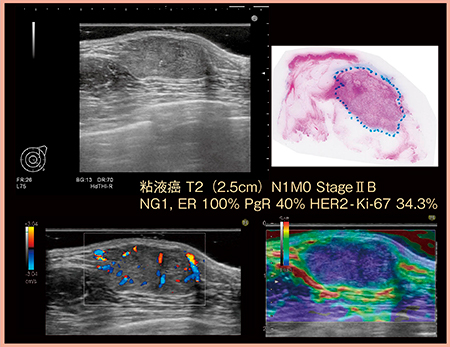

最近の超音波診断装置はかなり改善されているものの,本来,超音波は浅部の病変にフォーカスを合わせづらい。そのような場合は,音響カプラーやハードゼリーを用いて物理的に距離を取ることで,浅部の病変でも明瞭に描出することが可能となる(図1)。

図1 浅部病変の良好な描出